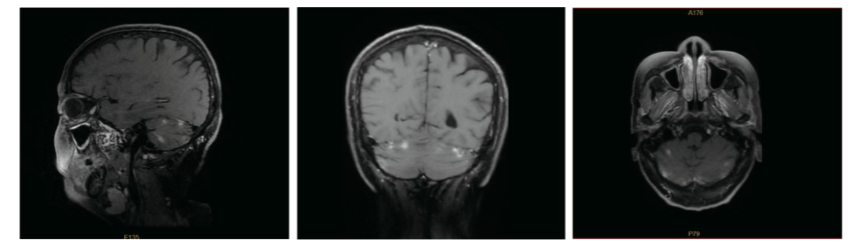

患者持续无病生存至2025年1月,期间出现持续性头枕部疼痛。在外部机构进行的脑部CT扫描显示强化病灶,符合脑转移特征,而再次分期CT未显示颅外复发。此时ECOG体能状态评分为1分。

4.png图3.2025年4月6日脑部增强MRI:双侧小脑半球可见多发强化病灶,符合脑转移瘤表现。

2025年1月15日,患者的全身治疗方案改为口服吡咯替尼400mg qd+卡培他滨 1.0g/m² bid,每21天为1个周期,第1-14天给药。治疗6周后,于2025年4月6日在我院进行的脑部MRI显示疾病稳定,无新发病灶。